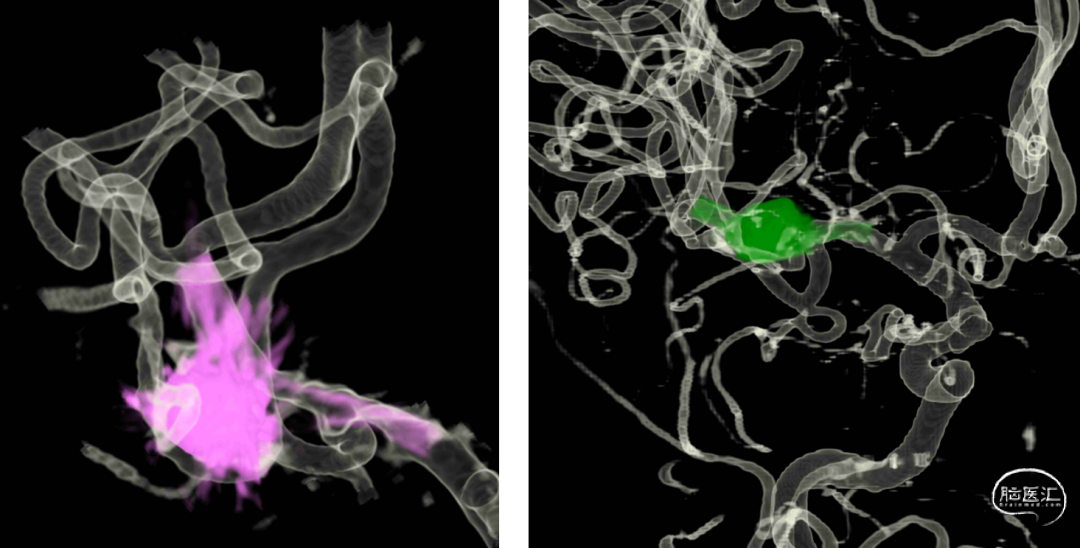

⇨FD结合弹簧圈动脉瘤栓塞术

Lattice 2.6x18

泰杰 6mm*20cm 3D、 泰杰4.5mm*12cm 3D、 泰杰3mm*6cm 3D